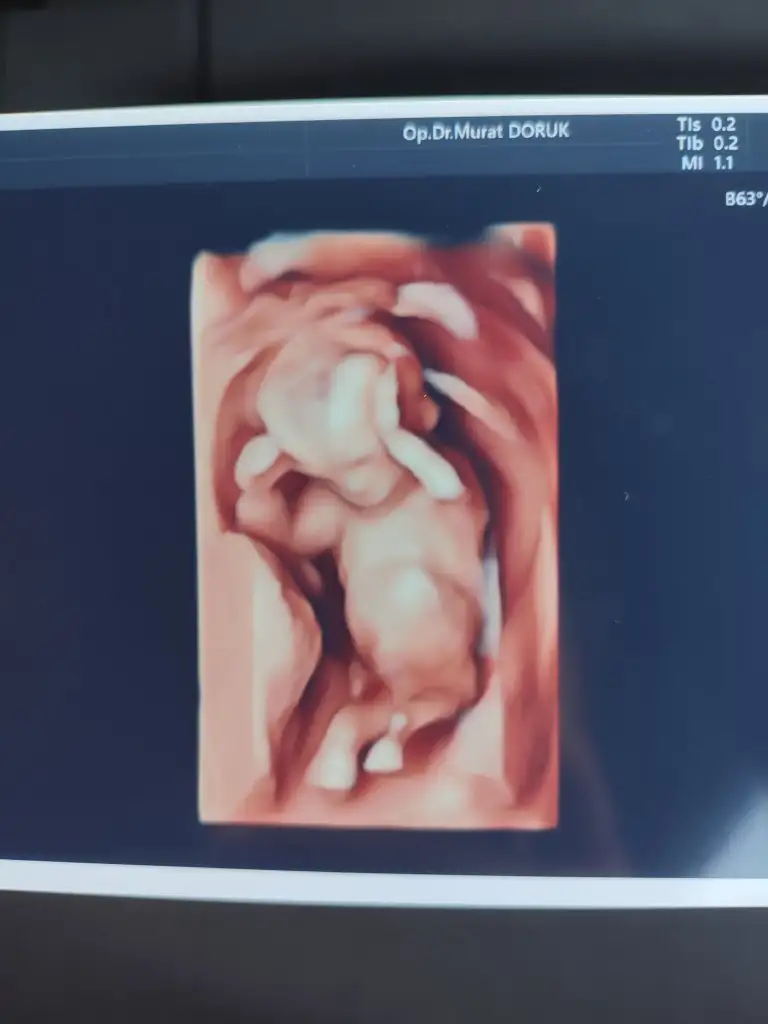

T temmuzekim çok çok geçmiş olsun Rabbim evladina uzun ömürler versin insallah ♥️ Hatirlarsaniz hamileydim bitane güzel kızım vardı şimdide yakışıkli bir oglum olucak inşallah şükürler olsun 😍bir kız bir erkek konuyu kapatırım 🙈

Zaman cok hızli geciyor 17 haftalik olduk bile teyzeleri :KK36: